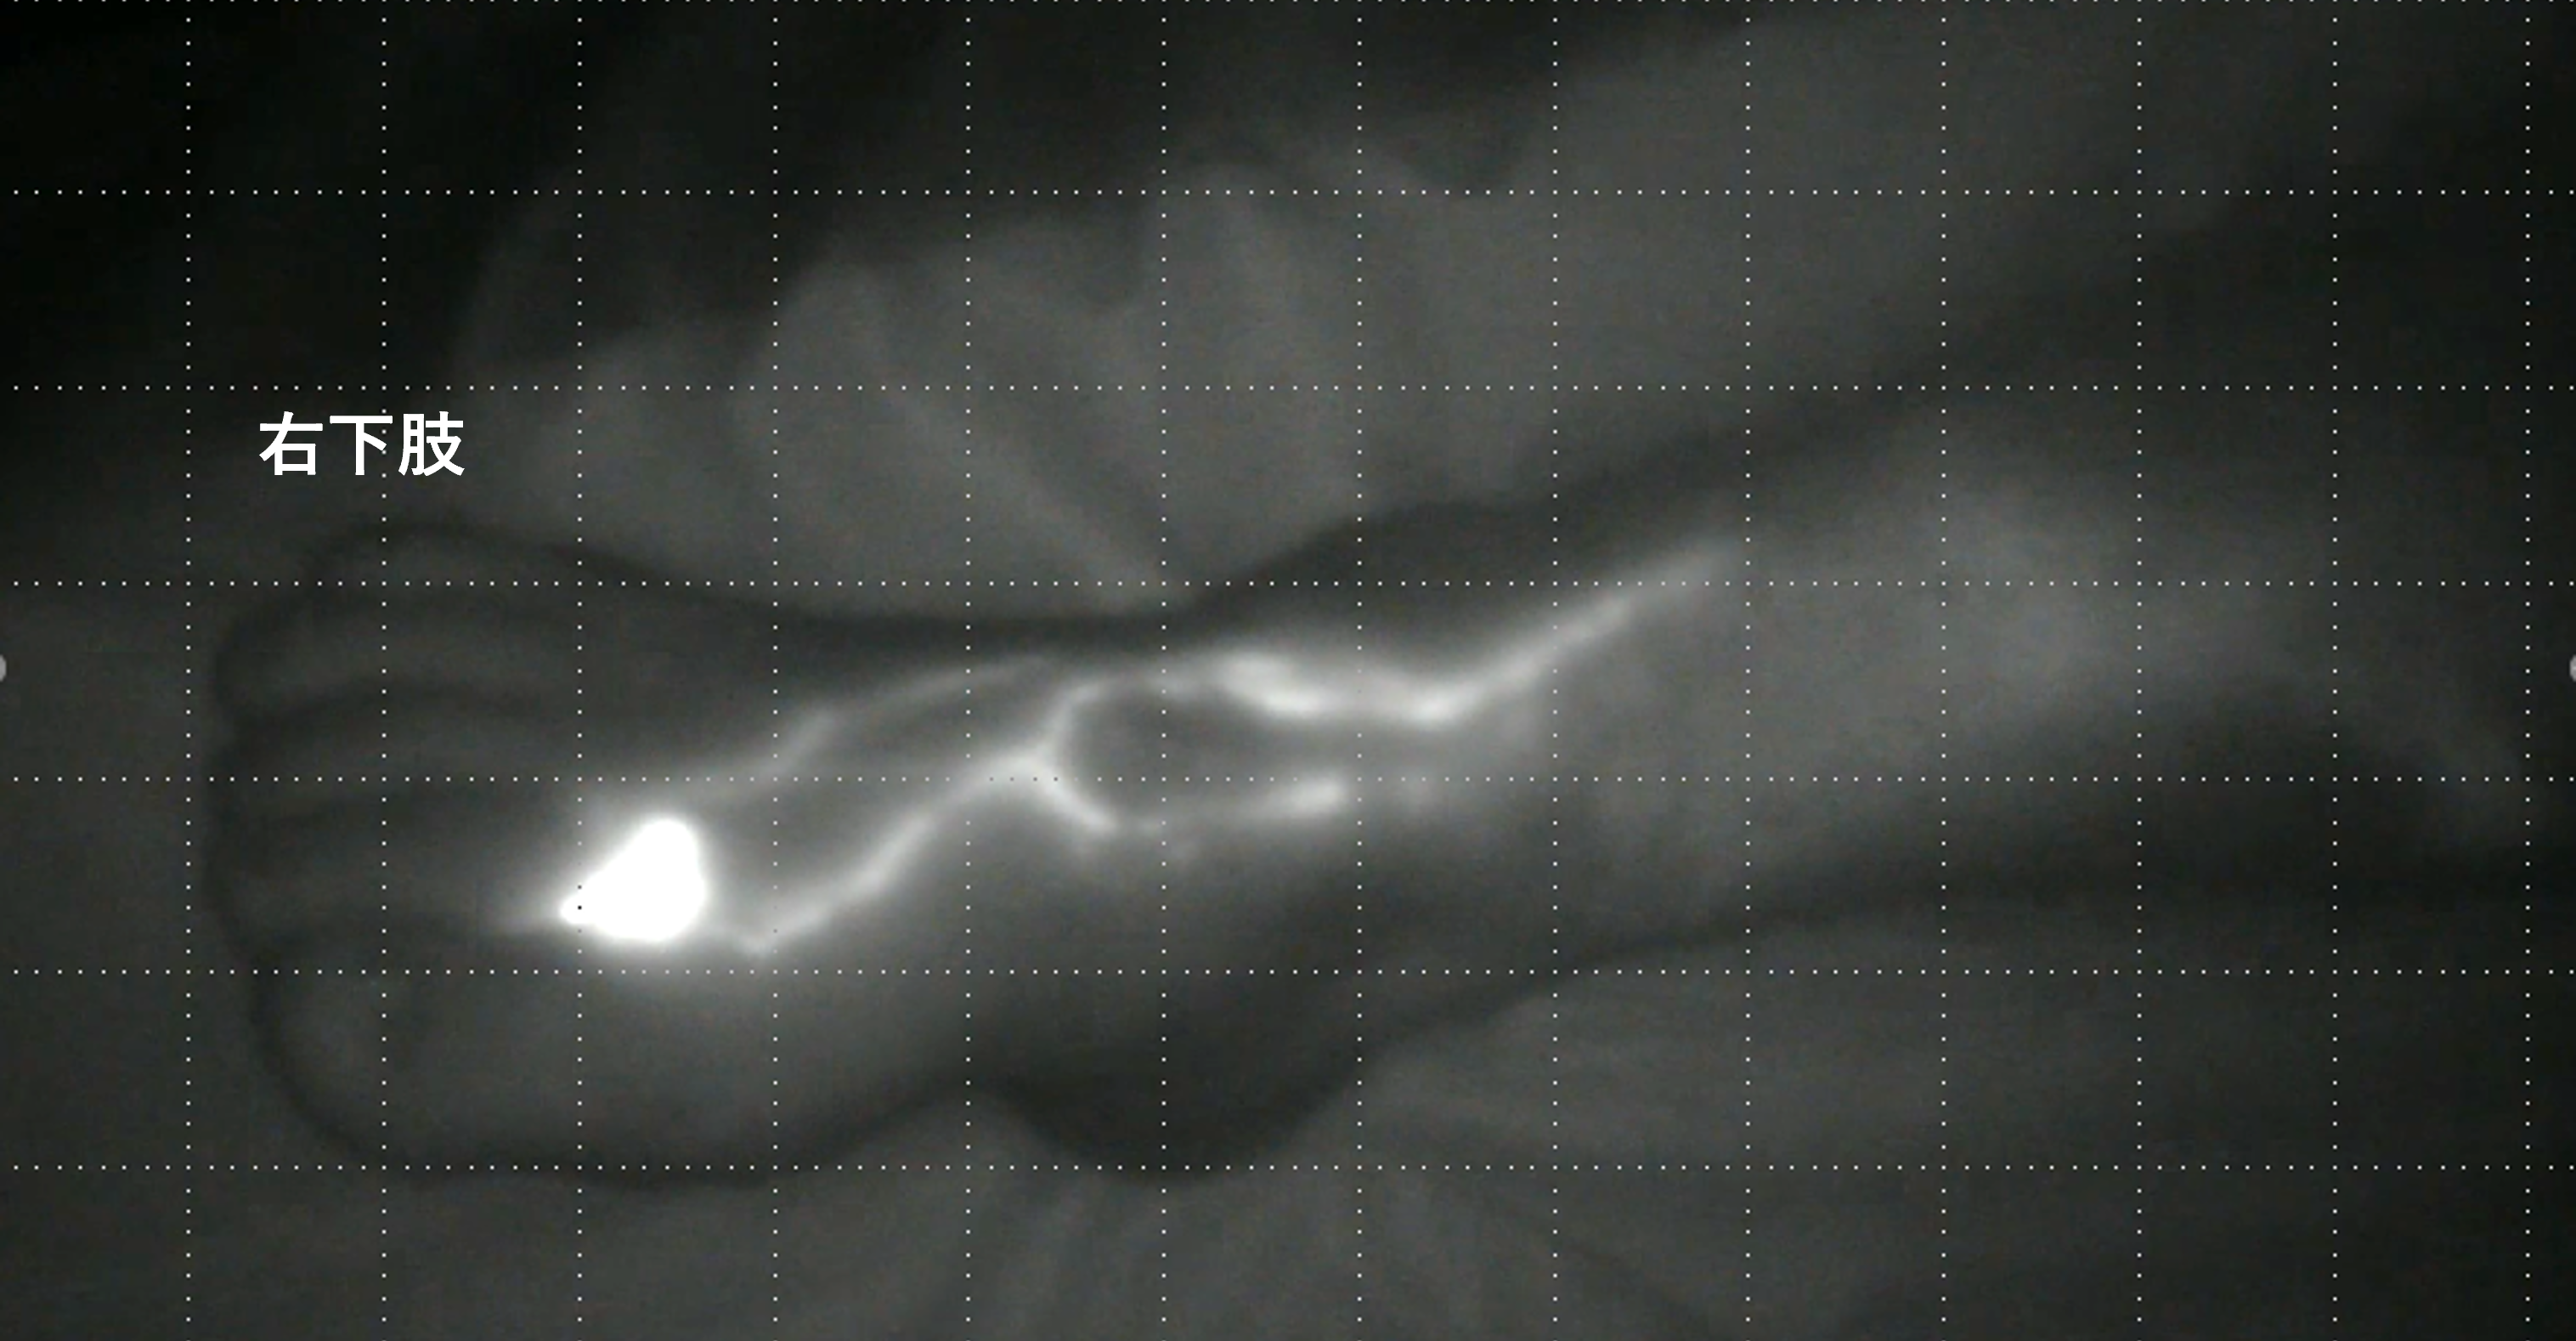

当院ではICG検査を行い”リンパ浮腫"の診断を行っています。

ICGは以前から肝機能の検査に使われていた薬剤です。

ICGを皮下に注射すると近くのリンパ管内に入り、流れます。

この流れを小型赤外線カメラで観察することができ、それ利用するのが「ICG検査」です。

リンパ管機能検査の中で唯一の保険適応が通っているリンパシンチグラフィと比較するとICG検査は自費の検査になりますが、初期のリンパ浮腫にも感度が良く、軽微なリンパ管機能異常も検出可能です。